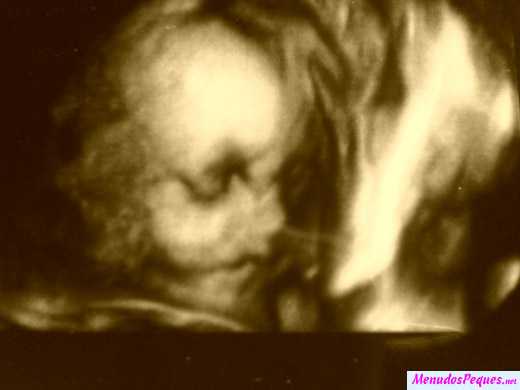

Ileana nos envió la ecografia de su bebé, Arianna Carolina, con 27 semanas de gestación, desde Caracas, Venezuela.